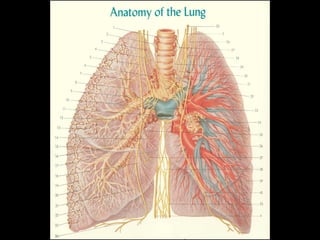

O documento fornece uma lista de estruturas anatômicas que podem ser visualizadas em uma radiografia de tórax, incluindo ossos, partes moles, pulmões, pleura, diafragma, coração, vasos sanguíneos e vértebras. Ele também menciona técnicas radiográficas como inspiração, rotação e uso de contraste.

- 5. ar osso Soro fisiológico Contraste radiológico Densidades radiológicas

- 9. inspiração 1 2 3 4 5 6 7 8 9 10

- 13. partes moles

- 14. mamas

- 15. omoplatas

- 16. ossos

- 18. cúpulas

- 22. hilos

- 23. pulmão/pleura

- 24. árvore brônquica artérias pulmonares (com contraste)

- 29. diafragmas

- 30. pulmões e pleura

- 31. pleura – cisuras

- 33. hilos